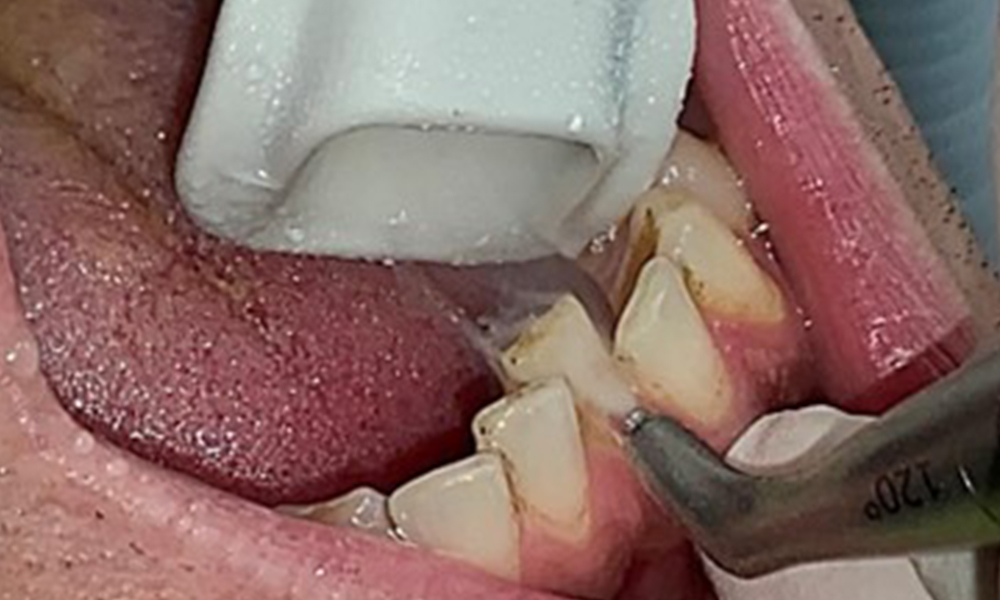

Obiectivul planului trebuie sp fie controlul riscului de boală, prin îndepărtarea biofilmului sub- și supragingival. Instrumentarul va fi ales în funcție de particularitățile pacientului. În primul rând, tartrul și eventualele concrețiuni vor fi înlăturate cu ajutorul pieselor cu ultrasunete și/sau manuale (Fig. 10).

Discolorările datorate consumului de nicotină și ceai pot fi îndepărtate cu ușurință cu ajutorul unui echipament air-flow (Fig. 11).